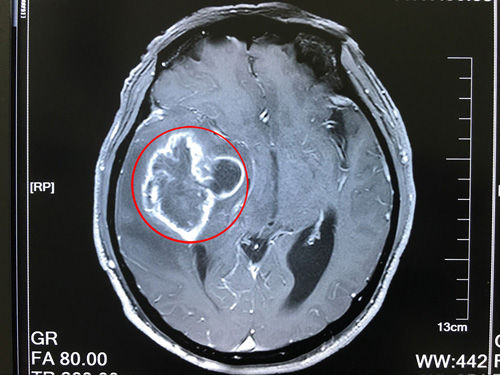

患者術(shù)前核磁影像:右側(cè)顳葉占位,右側(cè)高顱壓,大腦鐮疝

到院后,沈建康教授接待了薛老漢,看了他的影像資料,詢問了病史病情后,安排他完善了相關(guān)檢查;颊咦≡汉,沈教授將患者的病情,手術(shù)預(yù)后、以及風(fēng)險和家屬做了溝通。他說:膠質(zhì)瘤是惡性腫瘤,現(xiàn)在患者的膠質(zhì)瘤已屬于3-4級,非常高危,如果不及時做手術(shù),后果將不堪設(shè)想。

臨床上,CT診斷膠質(zhì)瘤病較為困難,MRI(核磁共振成像)在發(fā)現(xiàn)和顯示腫瘤范圍方面比CT更為清晰和敏感。手術(shù)是治療膠質(zhì)瘤的重要手段,其目的是提高患者生存質(zhì)量和延長生存時間,降低致殘率和死亡率。